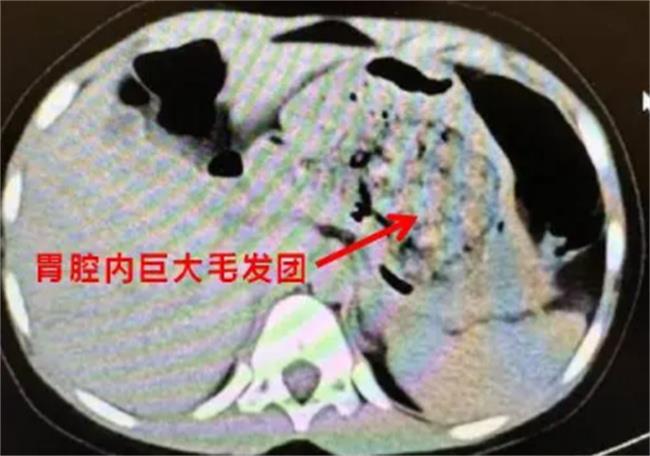

近期,位于浙江台州一名5岁女童连续三天腹痛不止,被紧急送往医院接受治疗,据医生检测,发现该女童是由于长期吃下大量头发,导致胃内头发形成毛团,巨大的毛团导致胃肠道堵塞,进而引起腹痛,经过医生的手术治疗,目前该女童胃内发团已被取出。

这名女童从小就有吃头发的习惯,在刚开始的时候家人并未注意,随着时间的不断加长,孩子的腹痛情况出现的更加频繁,疼痛更剧烈,频繁的疼痛已经开始影响女童的日常生活,经常因疼痛难忍而无法入睡,这种将头发吃入胃内形成发团,在医学上又被称之为“长发公主综合症”。

长发公主综合症患者经常会无法抑制的吃下自己的头发,长时间摄入大量的头发导致堆积在胃中无法被消化,逐渐形成毛发团,进而导致胃肠道堵塞,对此,医生表示,这种疾病出现的原因与个人习惯有一定的关联,也和孩子的身体健康有着一定的关联。生理上、环境上和心理上等多方面因素也会导致这种罕见疾病的出现,比如锌元素缺乏和缺铁性贫血以及缺乏父母的关爱等外部元素也会导致这种疾病的出现,长发公主综合症也被称之为“异食癖”,处于恶劣环境下的孩子有可能会产生异食癖,因此家长们在日常生活中一定要更加注意孩子的饮食健康,若发现孩子有吞食头发或摄入其他异物的行为,一定要及时制止,并带孩子前往专业的医院接受检测。